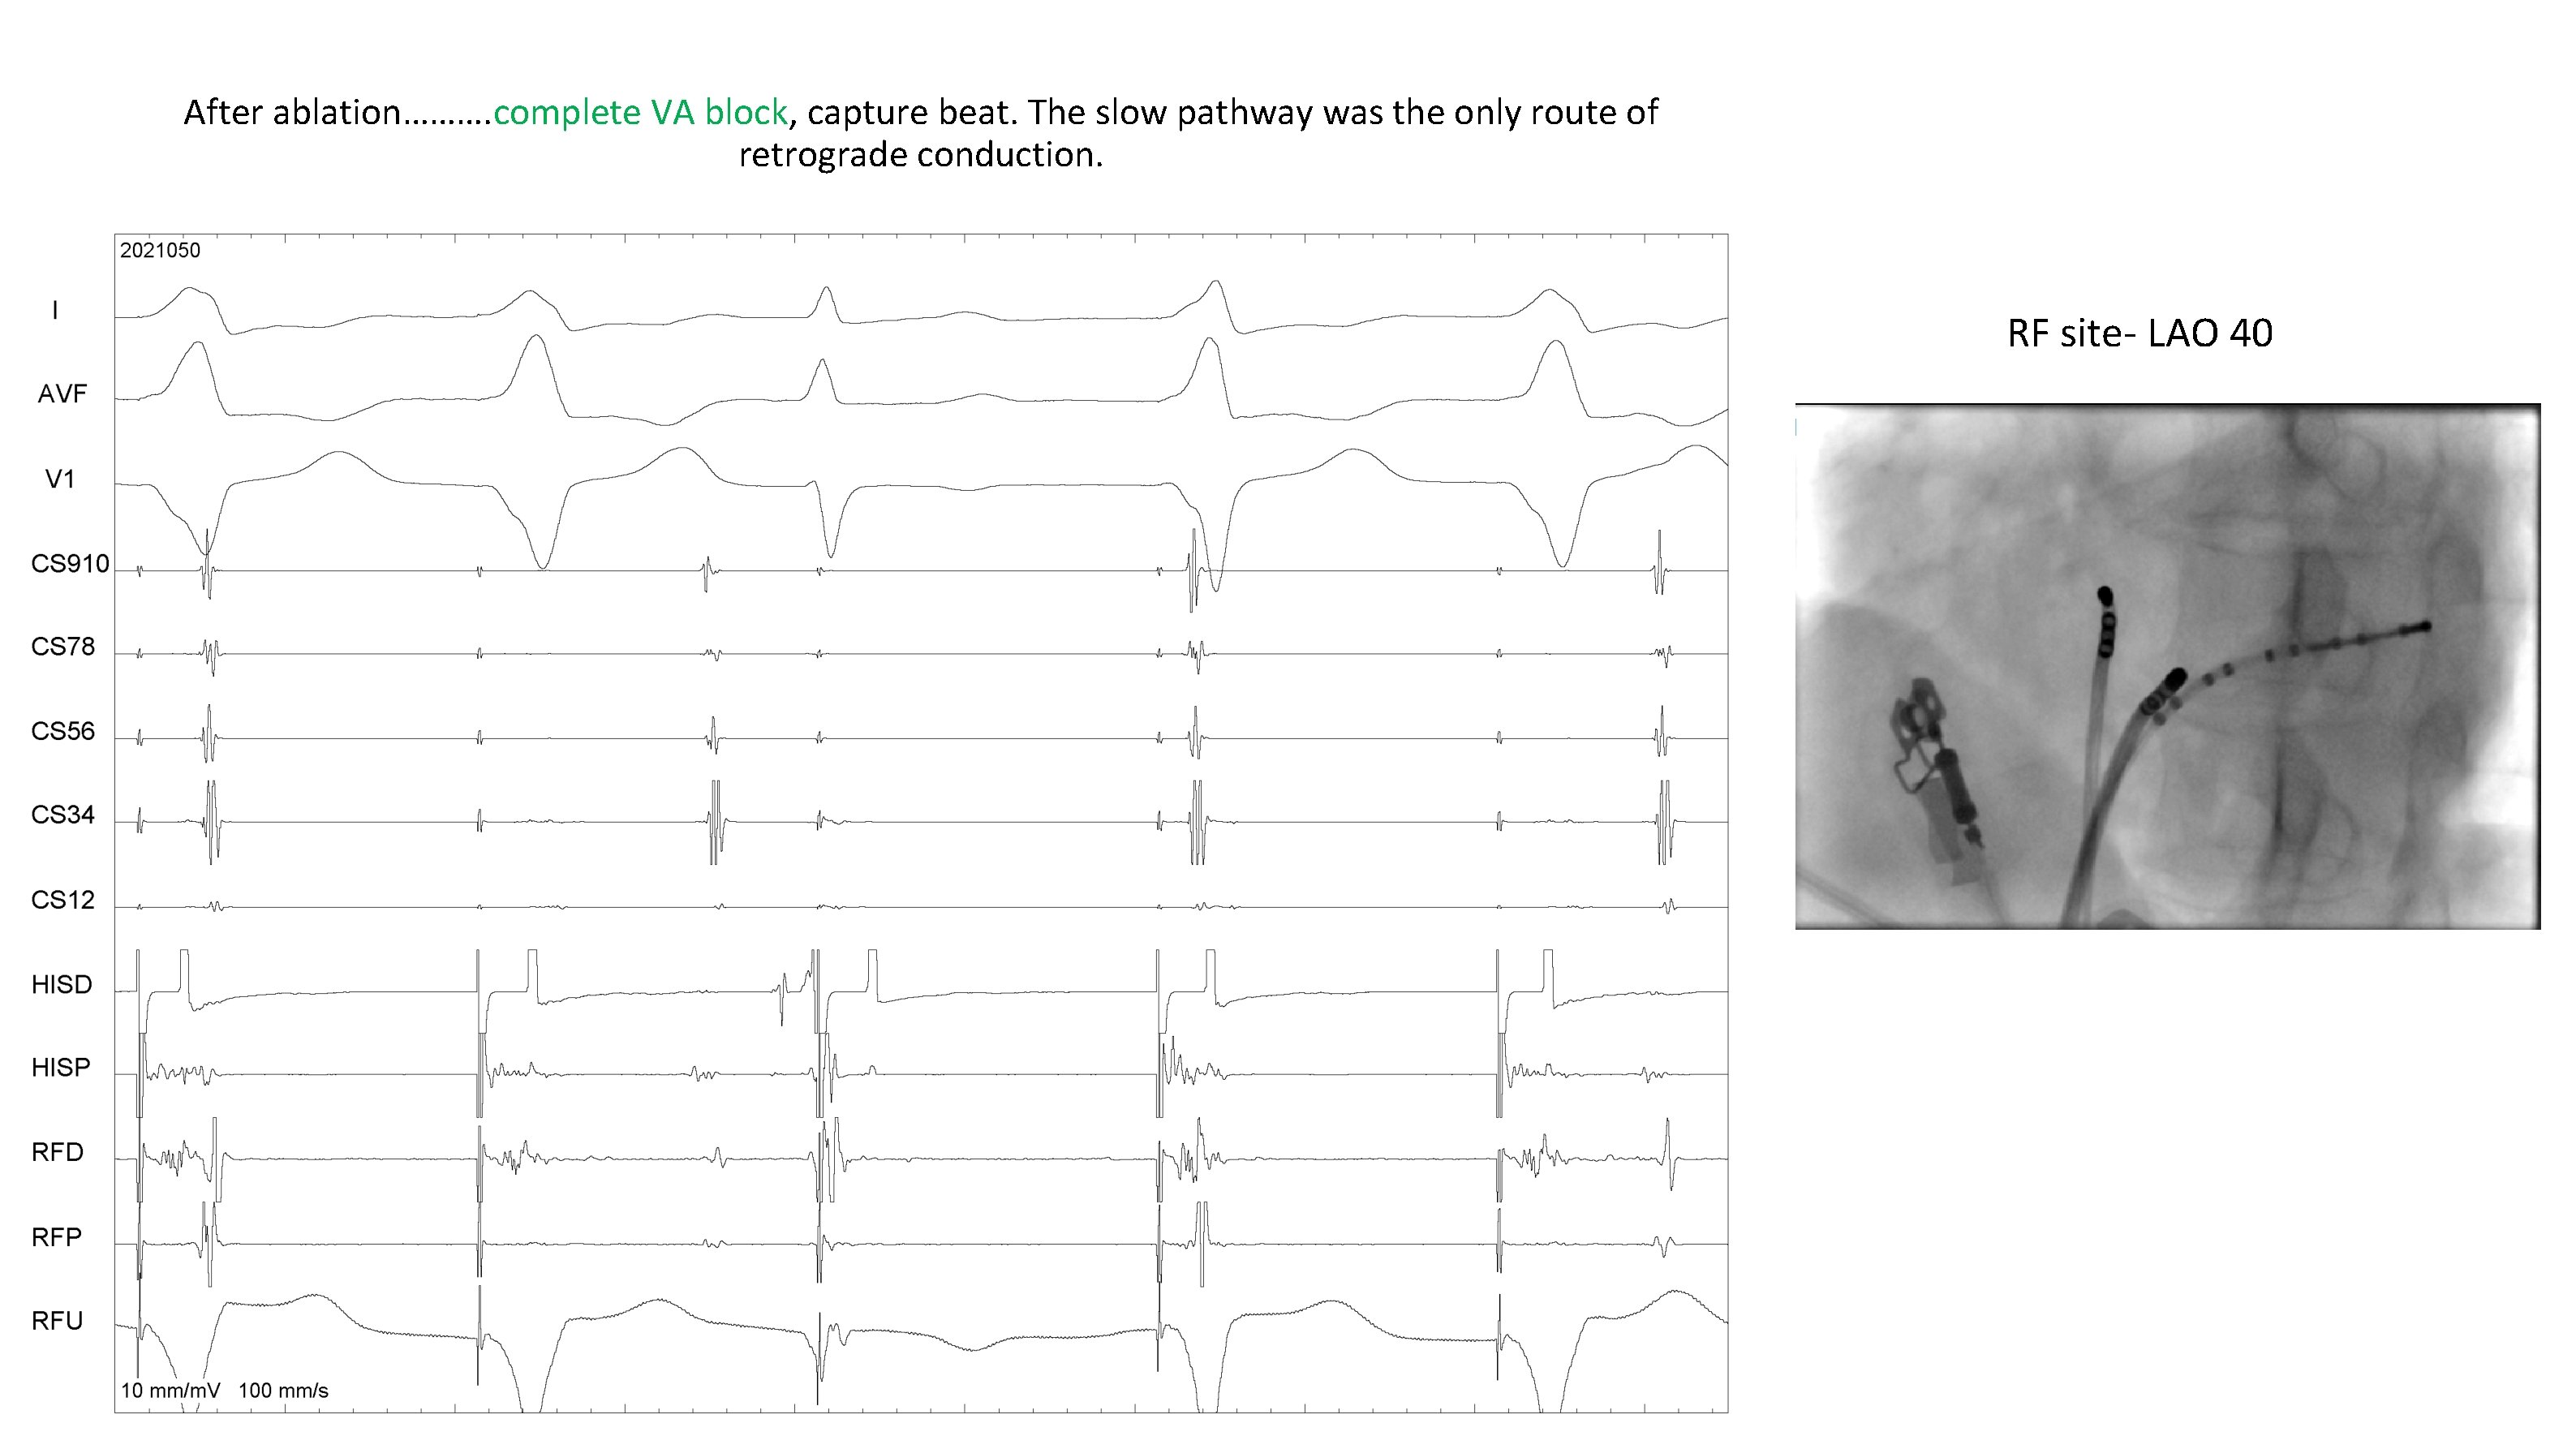

After ablation………. complete VA block, capture beat. The slow pathway was the only route of retrograde conduction. RF site- LAO 40

RF signal- likely site? LAO 40 , 6 o clock, Below CS os RF energy- successful elimination of the retrograde slow pathway resulting in termination of tachycardia